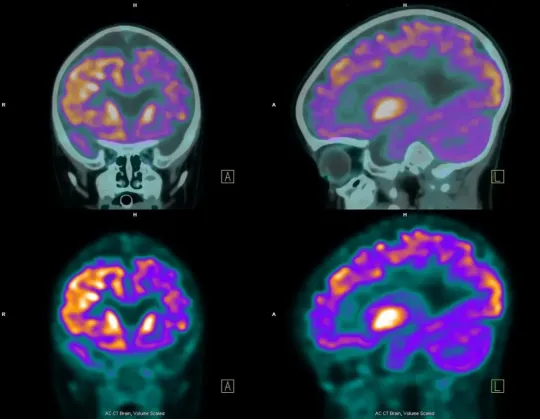

PET圖像

在進行腫瘤診斷時,首先要給患者注射一種顯影劑,叫做氟代脱氧葡萄糖(簡稱18F-FDG或FDG)。氟化脱氧葡萄糖的意思是,把葡萄糖的一個羥基即-OH,用氟的放射性同位素F-18取代。這種同位素具有放射性,會發生β+衰變,射出正電子。

這跟癌症檢測有什麼關係呢?癌細胞跟正常細胞的區別是,它的代謝更旺盛,對葡萄糖的消耗更高。所以腫瘤患者在注射氟化脱氧葡萄糖後,癌細胞聚集的部位會攝入更多的氟化脱氧葡萄糖。我們利用PET檢測出放射性強的部位,就可以確定腫瘤的位置,從而進行針對性的治療。